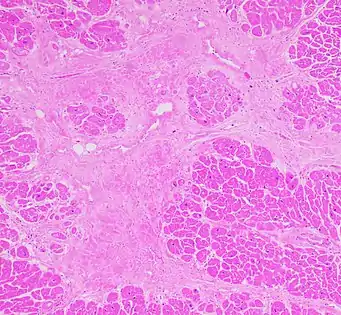

Cardiac fibrosis commonly refers to the excess deposition of extracellular matrix in the cardiac muscle, but the term may also refer to an abnormal thickening of the heart valves due to inappropriate proliferation of cardiac fibroblasts.[1] Fibrotic cardiac muscle is stiffer and less compliant and is seen in the progression to heart failure. The description below focuses on a specific mechanism of valvular pathology but there are other causes of valve pathology and fibrosis of the cardiac muscle.

Fibrocyte cells normally secrete collagen, and function to provide structural support for the heart. When over-activated this process causes thickening and fibrosis of the valve, with white tissue building up primarily on the tricuspid valve, but also occurring on the pulmonary valve. The thickening and loss of flexibility eventually may lead to valvular dysfunction and right-sided heart failure.